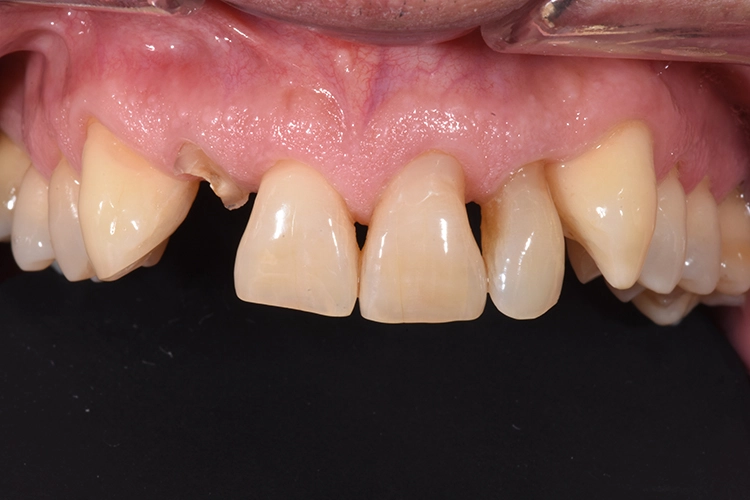

Fall 2: KFO-Extrusion

Dr. Blume

Ihr wurden die verschiedenen Behandlungsmöglichkeiten erklärt. Die Patientin wünschte sich den Erhalt der eigenen Zähne. Aufgrund der Breite der Lücke und schwierig zu schienender Situation entschieden wir uns für eine kieferorthopädische Extrusion der beiden Wurzelreste.